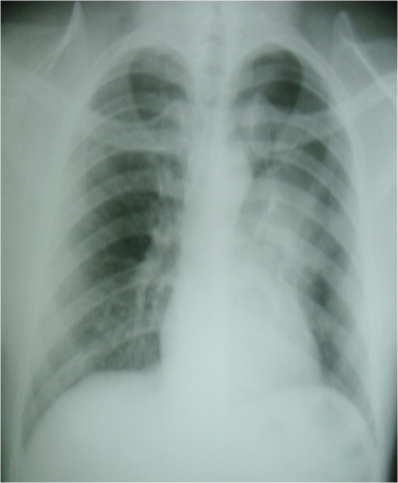

A 25year old male from SE, Nigeria presented at the cardiothoracic unit with a 4years history of cough, hemoptysis and shortness of breath. He did not lose weight or sweat excessively. He has never smoked and is not a known asthmatic. He had a complete course of anti-tuberculosis drugs but there was no improvement. He looked well nourished and active. There was a dull percussion note and a reduced air entry in the left upper lung zone. Chest x-ray showed a significant left hilar opacity (Figure 1). Chest CT scan revealed an oval mass in the left upper lobe with a widest diameter of 6.19cm obstructing the left upper lobar bronchus with collapse of the upper lobe segments. There was no enlarged left hilar or mediastinal lymph nodes (Figures 2-4). A trans-thoracic needle biopsy reported typical BCT (Figure 5). He had a left upper lobectomy with regional lymph node dissection through a left postero-lateral thoracotomy. The left lower lobe was free of any tumor (Figure 6). Left upper lobar mass and hilar lymph nodes were sampled and reported as typical BCT (Central type) with tumor free resection margins and no lymph node involvement (Figure 7). They tumor cells strongly expressed broad spectrum cytokeratins, synaptophysin, CD 56 and NSE (Figures 8-11).

Figure 1 CXR showing left hilar opacity.